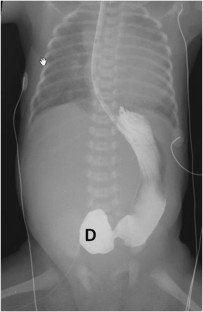

Herman, T., Siegel, M. Giant omphalocele, intrinsic duodenal obstruction. J Perinatol 31, 293–295 (2011). https://doi.org/10.1038/jp.2010.163